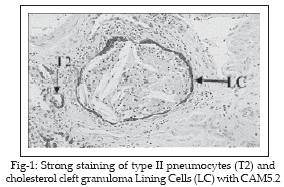

Half of the cases studied exhibited the presence of numerous dispersed cholesterol cleft granulomas (Figure-1). These were discrete, compact, uniform in size and present mostly in areas of alveolar wall thickening. The granulomas were universally present in alveolar spaces. They were never observed within alveolar walls nor in relationship to blood vessels. Typically the granulomas contained central clefts (mean length 52.6µm, range 18.0 109.3µm) surrounded by mono-and multinucleated cells which were CD68 positive, whereas the cells outside the granulomas and lining the alveolar walls were negative with this antibody (Figure-2). In contrast these latter cells were both AE1/AE3 and CAM5.2 positive (Figure-3). Elsewhere, in alveolar spaces not containing granulomas, there were occasional small populations of alveolar macrophages also showing CD68 positivity.

19 Currently there are no available data on cytokine elaboration by pulmonary cholesterol cleft granulomas.This immuno histochemical study confirmed that the intra-alveolar cell populations in NSIP were composed predominantly of CD68 positive cells. It showed that the giant cells were also CD68 positive, but were cytokeratin negative. In contrast, the cells lining the alveolar spaces containing granulomas were cytokeratin positive (AE1/AE3 and CAM5.2), indicating that these were type II pneumocytes and showing that these cells had completely replaced type I cells at these loci. In addition, it is known that macrophages and macrophage polykaryons have distinctive glycoprofiles and that pneumocytes types I and II can be distinguished by their profiles.